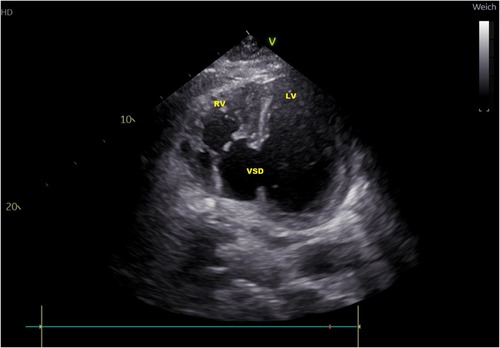

In subsequent echocardiography and cardiac computed tomography, the full dimensions of the ventricular septum defect were visualized. We discussed the VSD extensively with our adult and pediatric cardiologist colleagues and our congenital cardiac surgeons. Since dimensions were measured with 4.9 × 5 cm and its very close localization to the atrioventricular valve area (Figures 1, 2) not leaving a sufficient rim for placing either sutures or patch-sutures, the VSD was considered untreatable. In light of very few prospects for success, we considered a surgical VSD exploration and attempt of closure as way too risky for the patient.

Figure 1. CT-scan: ventricular septal defect (VSD) directly under the valvular plane, volume-loaded left and right ventricle (LV, RV).

Figure 2. Transthoracic echocardiography atypical two-chamber view: ventricular septal defect (VSD), loaded left and right ventricle (LV, RV).